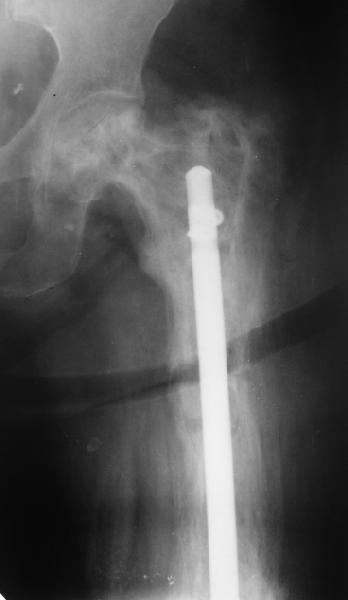

Re: перелом бедра на фоне болезни Педжета

Еще один пример. Пациентка с юга России, прислала рентгенограммы через год. На сегодня прошло 2 г. 8 мес. после операции. Несмотря на не очень убедительный процесс сращения, пациентка ходит. Учитывая остеопороз при Педжете, решили, что динамизировать вообще не нужно.